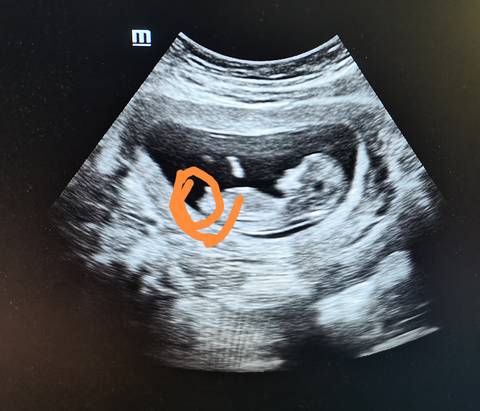

能看懂的宝妈,这是宝宝的脚还是生殖器官

你好。我们是判断不了男宝宝跟女宝宝的,孕期定期检查,我觉得宝宝健康就好的。祝心想事成 。